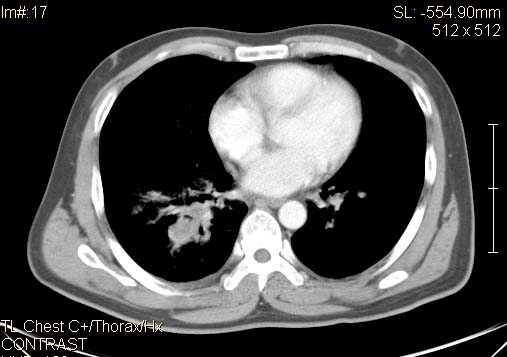

以下是引用qc80012345在2007-4-17 12:33:00的发言:[br]右肺下叶周围型肺癌伴肺门及纵隔内淋巴结转移;比较清楚。

以下是引用qingyuan在2007-4-17 14:19:00的发言:[br]右肺下叶外侧后段胸膜下区节结样病变、分叶、内可见空洞,壁厚薄不均,胸膜凹陷、肺门周围区纹理增粗、僵硬、并近似小结节样改变,肺门区软组织节结、纵膈淋巴结肿大,患者病史长、抗炎治疗无好转炎性改变基本排除,考虑:右肺下叶周围型肺癌伴纵膈及右肺门区淋巴结转移、肺内淋巴管受侵。